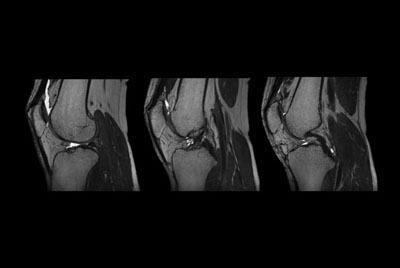

SmartSpeed Traumatic Knee imaging

SmartSpeed 2 min Knee imaging

Knee ACL repair

Knee with lesion

High quality Knee imaging in short scan times

Knee imaging with Compressed SENSE

Knee exam with/without Compressed SENSE

Knee Imaging with Cartilage Assessment

Metal Imaging of the Knee

3D Knee imaging with MSK VIEW

Knee imaging

Comprehensive 3D knee imaging with MSK VIEW